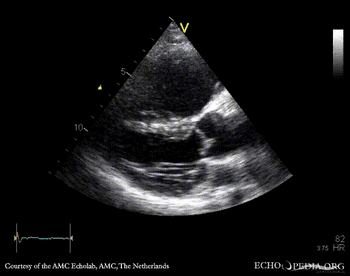

E00348.gif E00349.gif

A4CH: stiff, immobile tricuspid valve A4CH: severe tricuspid regurgitation